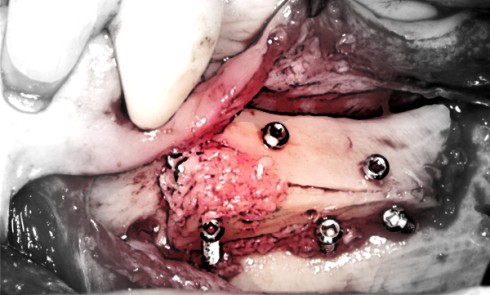

Article réservé à nos abonnés Passivation des lambeaux postérieurs mandibulaires en chirurgie d’augmentation osseuse horizontale ou verticale :

Dans l’implantologie moderne, les greffes d’augmentations osseuses mandibulaires sont parfois incontournables et ce, malgré les possibilités offertes par la chirurgie...